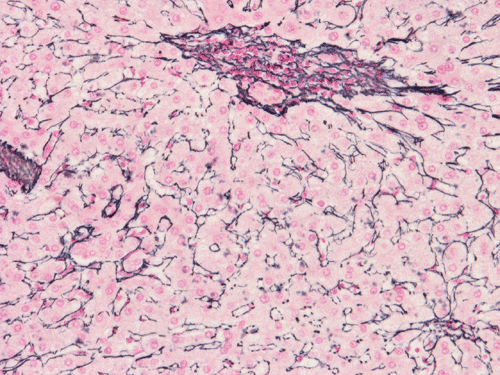

Histologically, the grossly notable nodules correspond to islands of cells separated by dense fibrous tissue  (Panel B). On medium magnification, the islands of cells have smooth, pushing margins (Panel C). The cells are quite similar to normal hepatocytes except that these islands do not have the general architecture of normal liver (Panel D). The liver plate varies from one to three cell thick is well demonstrated by reticulin stain (Panel I). In some areas there are some entrapped ductular structure consistent with bile ductules (Panel E and F) and they are well demonstrated by immunohistochemistry for cytokeratin 7 (Panel J and K). Most of these ductules are found around the fibrous scar or septa or at the edge of the nodules. Many abnormally large blood vessels are also noted and many of them are seen in the fibrous central scar (Panel G and H).

The histopathologic triad of FNH is bland hepatocytes without abnormal architecture, preserved reticulin network, the presence of bile ductules, central scar with fine fibrous septa radiating out, and the presence of large and abnormal blood vessels surrounded by a zone of connective tissue.

Histologically, the cells in FNH are  almost identical to the normal hepatocytes surrounding hepatocytes. The reticulin network is preserved and the liver plate varies from one to three cells thick. The cells in FNA  may possess increased cytoplasmic glycogen content, focal steatosis, bile stasis, lipofuscin, iron pigment, copper deposits and Mallory bodies 4.   The central scar is composed of dense collagenous fibrous tissue with a variable number of tortuous thick-walled arteries. Fibromascular hyperplasia and myxoid degeneration are often found in these vessels.

FNH and adenoma share the common features of occurring in young woman during their reproductive age and are related with the use of contraceptives. Both of them share the similar cytologic features. The cells are very similar to the normal surrounding hepatocytes. The cell plate are one to three cells thick and is best demonstrated by reticulin stain. Adenoma, however, has even stronger inclination to occur in woman. FNH and adenoma, however, have different imaging and scintigraphic characteristics. FNH reveals a homogenous enhancement with a central scar on CT and MRI and normal or increased uptake on Tc-sulfur-colloid scintigraphy. While adenoma appears as a hyperintence heterogenous mass in image and has no uptake in scintigraphy. The central scar is also helpful on histologic examination. It should be noted that the scar in small FNH may not be obvious. A high level of suspicion and careful examination is mandatory. Histologically FNH usually have ductule proliferation and hyperplastic and abnormal large vessels. The ductules are usually found in the fibrovascular areas and often at the edge of the tumor. Although large vessels are often seen in adenoma, there is no significant connective tissue zone around them. In contrast, vessels in FNH are abnormally large and are surrounded by a zone of connective tissue. Adenoma can have occasional fibrous septa which tends to be discontinuous. The fibrous scar and septa in FNH is more prominent.